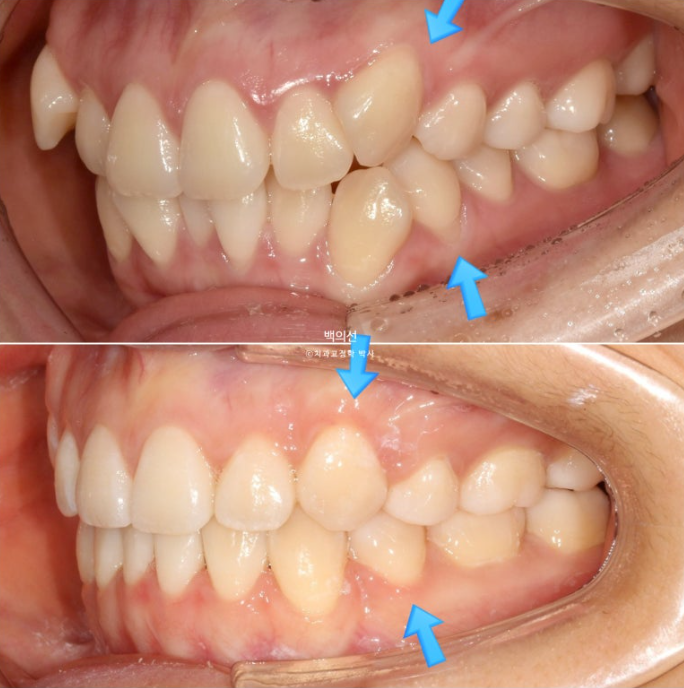

23년 7월 교정을 위해 내원한 환자분입니다.

덧니가 심한 편 입니다.

잇몸이 얇아서 20대 초반의 나이임에도 불구하고 덧니를 포함한 일부 치아의 잇몸이 내려가 있습니다.

군데군데 잇몸이 내려가 뿌리 노출된 부분들이 있습니다.

교정치료로 한 번 내려간 잇몸이 다시 차오르지는 않지만 , 발치교정을 통해 최소한 뿌리를 안쪽으로 넣어주어

더 이상 내려가는 것을 막아줄 순 있습니다.

덧니 펼 공간이 많이 필요하고 잇몸도 얇아 비발치로 치료 시 잇몸이 더 내려갈수도 있는 상태입니다.

초진 입매를 보면 입술돌출은 거의 없지만 상기의 이유로 작은어금니 4개 발치교정을 결정하였습니다

환자분은 치주건강상의 이슈로 발치의 이유는 납득을 하지만 발치로 인해 입이 너무 들어가지 않게 해달라고 요청하셨습니다.